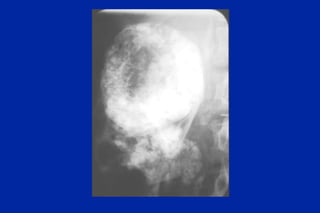

Este documento resume los principales tipos y técnicas de angiografía. Describe brevemente la angiografía, arteriografía, flebografía y linfografía, así como las técnicas de contraste y materiales utilizados. También explica los principales accesos vasculares, la técnica de Seldinger, la angiografía por sustracción digital y algunas técnicas endovasculares comunes.